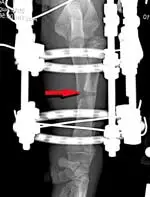

In this case, the treatment chosen was a partial closing wedge osteotomy (based on the CORA) and a gradual angular correction of the proximal radius via tensioning of a single olive wire positioned within a circular ring fixator, without the performance of an arthrotomy (Figure 3).

Figure 3: Frontal plane radiograph of the left antebrachium immediately after surgery showing the placement of the circular ring fixator on the limb with a single olive wire engaging the proximal radial segment. A closing wedge ostectomy has been completed at the level of the CORA (red arrow).

This procedure first required temporary proximal distraction of the humerus using a transarticular extension of the fixator to provide clearance for the radial head. Once the radial head was repositioned under the humeral condyle, the distraction of the humerus was discontinued and the transarticular component of the fixator removed (Figure 4). The fixator was maintained for 4 weeks until clinical union was achieved. At that point the fixator was removed.